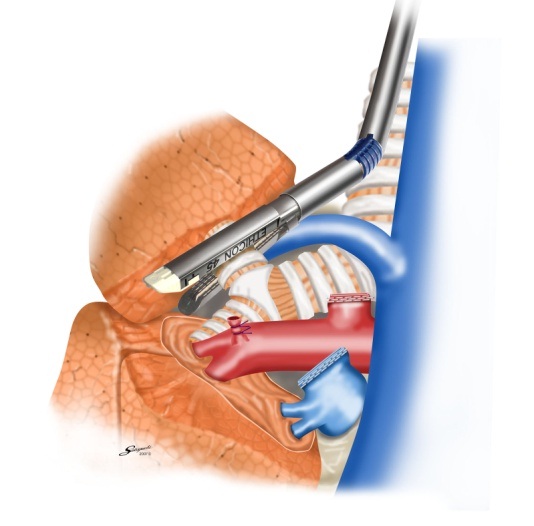

胸腔鏡手術の実際(右肺上葉切除時の自動縫合器使用例)

肺静脈切離

肺動脈切離

気管支切離

葉間切離